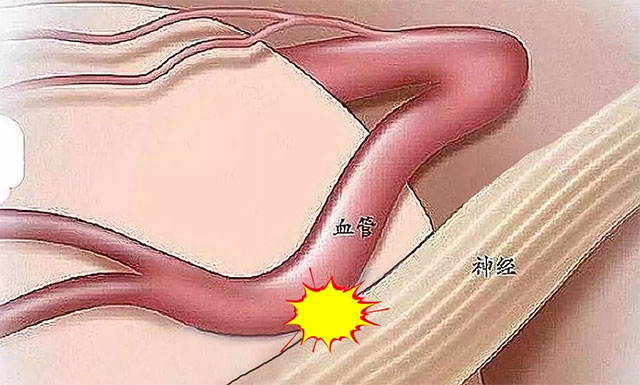

我们面部的神经支配着整个面部以及眼皮肌肉的运动,因此如果当面部神经受到刺激时,就会引起其支配肌肉的抽动。控制眼轮匝肌的,是一条面神经。当这条面神经“闹情绪”时,眼轮匝肌就无法收放自如,甚至可能出现“胡蹦乱跳”。

面肌痉挛病因比较明确,大多数患者是由桥小脑角区血管压迫面神经根部引起,还有部分患者可能由肿瘤、炎症或面神经炎等引起。

▲ 大多数面肌痉挛是因血管压迫面神经根部引起的